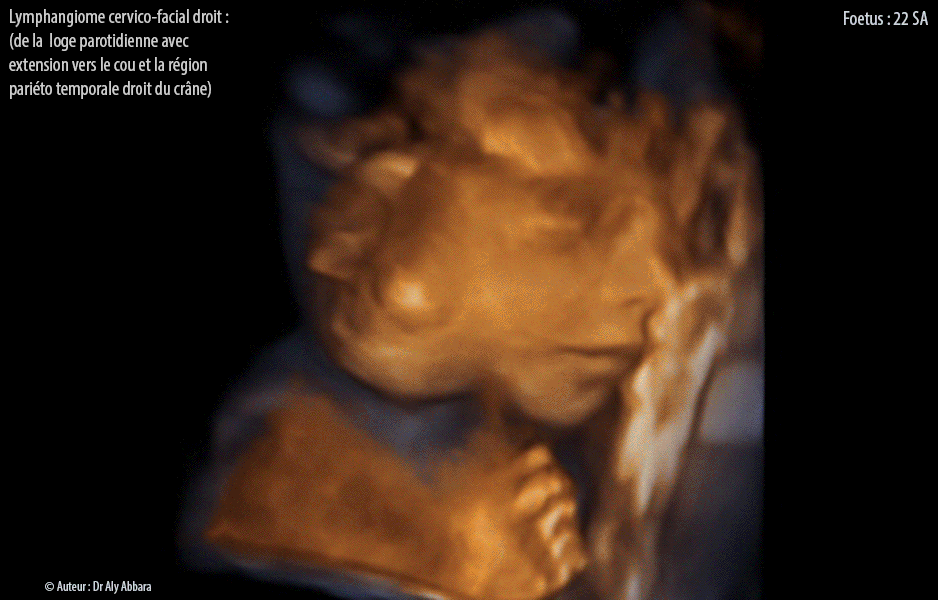

Lymphangiome micro et macrokystique cervico-facial droit - Grossesse de 22 SA - Images échographiques en 2D et 3D

Lymphangiome micro et macrokystique cervico-facial droit chez un fœtus âgé de 22 SA :

• Auto diaporamas (format MP4 et GIF) d'images échographiques animées montrant un lymphangiome poly-macro et microkystique cervico-facial, évoluant sous la peau et en profondeur à partir de la loge parotidienne droite avec extension large vers le haut, dans la région temporale droite, et vers le bas, dans le cou, où il s'infiltre dans la moitié droite de son épaisseur (sans dépasser la ligne médiane) et il atteint son tiers inférieur, mais tout en restant au-dessus du niveau des clavicules (donc ne pénètre pas dans le médiastin thoracique).

Sur les coupes frontales et axiales de l'étage inférieur du crâne et du cou, on peut constater que ce lymphangiome atteint en profondeur les bords latéraux du rachis cervical et la face externe de l'os temporal ce qui entraîne le soulèvement du pavillon externe de l'oreille droite. Ce lymphangiome atteint également les faces latérales externes droites des deux mâchoires (supérieure et inférieure). En profondeur, on observe aussi que la tumeur se trouve au contact avec l'artère carotide externe droite et la paroi latérale droite du pharynx.

Il existe également un léger œdème frontal.

Il s'agit d'un lymphangiome de 43 mm de diamètre antéro-postérieur et 23 mm d'épaisseur frontale et enfin 35 mm de hauteur (soit un volume d'environ 20 cm3).